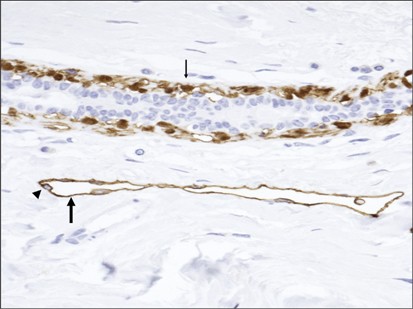

Previous studies have shown that proliferation assessed by either mitotic activity index or phosphohistone H3 has strong prognostic value.2, 3, 4 This is in agreement with gene expression array studies.5, 6, 7 For example, patients with a high proliferation index in general have a 3.5–5 times higher risk of developing and dying from distant metastases than those with a low proliferation.2 In spite of their prognostic superiority, neither mitotic activity index nor phosphohistone H3 obtain an optimal accuracy and only 30–40% of patients with high proliferation die from their disease. It is therefore important to evaluate whether other potentially important and biologically understandable features have independent (additional) prognostic value. Vessel invasion is an attractive option, and its prognostic value has been known for many decades as an important marker for breast cancer progression.8, 9 Lymphatic vessel invasion has been conventionally assessed on hematoxylin–eosin-stained sections, but this assessment tends to be subjective. Other studies have used immunohistochemistry to assess vessel invasion (for an overview, see Mohammed et al10). The monoclonal antibody D2-40 has often been used as a marker of lymphatic endothelium to identify tumor emboli in lymph vessels.11 However, D2-40 does not only stain lymph vessels but also breast myopethelial cells (Figure 1). The growth pattern of tumor cells surrounded by D2-40-positive myoepitelial cells generally enables distinction of ductal carcinoma in situ from lymphovascular invasion. However, D2-40 myoepithelial expression in small ducts completely filled by solid-pattern ductal carcinoma in situ can mimic the pattern expected for lymphovascular invasion.12 We have therefore used double staining for lymph vessels by D2-40 and p63 (which stains myoepithelial cell nuclei). D2-40+/p63+ are myoepithelial cells, whereas D2-40+/p63− structures are lymph vessels. This enables a more reliable differentiation between ductal carcinoma in situ and lymphovascular invasion.

Overview of the histological and separate immunohistochemical stainings for D2-40 and p63 on consecutive slides. A ductal carcinoma in situ (DCIS; arrow) surrounded by invasive ductal carcinoma (arrowhead). (a) Immunohistochemical staining depicting corresponding duct with D2-40 (b) and nuclear expression for p63 (c). Note cytoplasmic expression for D2-40 in myoepithelial cells.